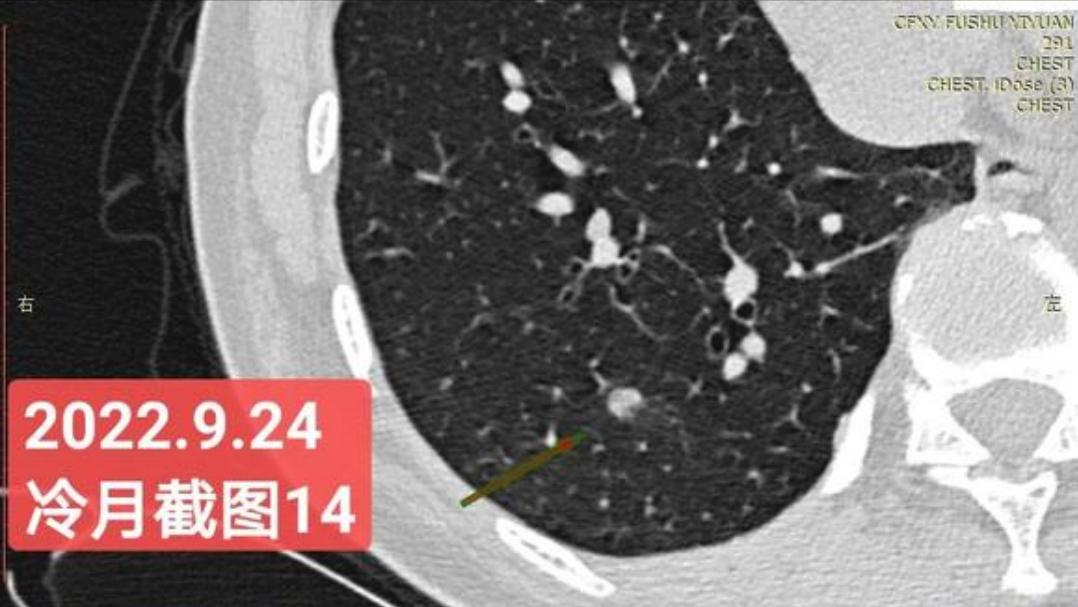

非常感谢戴主任和冷月等几位吧主的无私奉献,你们牺牲自己的休息时间,为广大患者排忧解难,你们对待病人,如同亲人一样,真的好感动!上次,在贴吧里咨询过戴主任关于我的肺结节情况,戴主任说,我右肺下叶那个结节高危。心里好害怕,距离上次CT间隔三个月,我又做了肺部CT,这次还要劳烦戴主任以及吧主们,帮我看看我的肺结节,严重吗?需要马上手术吗?

我昨天把我五次肺部CT电子版以及报告,发给了冷月吧主,昨天晚上,冷月吧主就为我截好图,发给我,非常令我感动,谢谢您冷月吧主,您辛苦了,您要多休息,不要太辛苦了。

我是21年7月做肺部CT,报告给报出0.5厘米肺结节。(但大夫说,20年就已经有那个肺结节了,因为小,报告没给报)。自发现肺结节后,吃了四个月中药,结节没有缩小,反而增大了。今年8月1日开始到现在,又吃了近两个月的蒙药了。 结节还是没有缩小,反而在增大。21年7月到现在,复查过3次肺部CT了。结节一直在增大。最近一次复查时间是2022年9月24日。

上次找戴主任贴吧咨询过,主任说我右肺下叶那个结节高危,距离上次CT,到现在三个月复查肺部CT。所以9月24日又复查做了肺部CT。

右下肺结节高危,肺窗已经到亚实性阶段CTR>0.5,纵膈窗可见实性,目前已经不属于异质混磨,而且PSN亚实性结节。